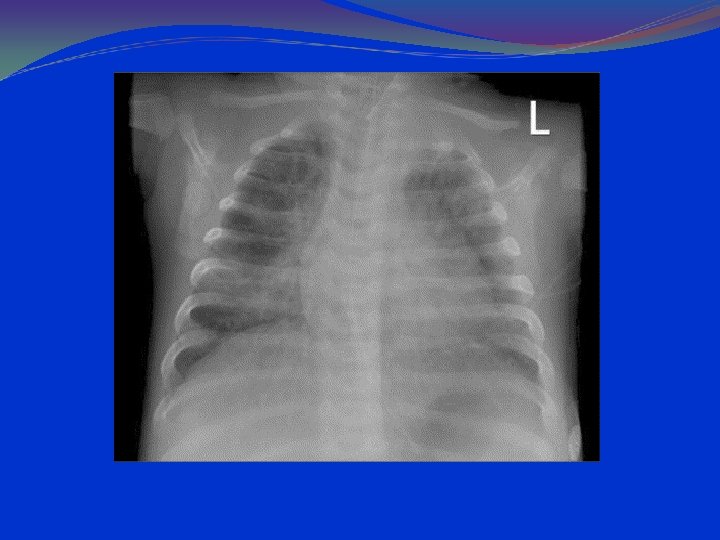

IMAGERY The typical radiological finding is a homogenous, non -segmental, circumscribed consolidation of lung tissue. The opacities are situated anywhere in the lungs, although they are located most often in the basal segments, and are unifocal or multifocal. An air bronchogram is often seen and is considered to be characteristic of pneumococcal pneumonia. The affected segments of the lung are not reduced in volume. Pleural involvement (pleural effusion) is not usual

CLINICAL FORMS Broncho-Pneumonia Common cause is staphylococcal infection. Bronchopneumonia is characterized by patchy exudative consolidation of lung parenchyma due to terminal bronchiolitis with consolidation of peribronchial alveoli. Bilateral (less often unilateral), patchy consolidation with intervening normal lung tissue. Lesion is more extensive at the base of the lung and often fuses together resembling lobar pneumonia (confluent bronchopneumonia).

IMAGERY INTERSTITIAL CONDENSATIONS CONFLUATION PROGRESSION TO ABCESS, EMPIEMA Restitutio ad integrum or pneumatocelae